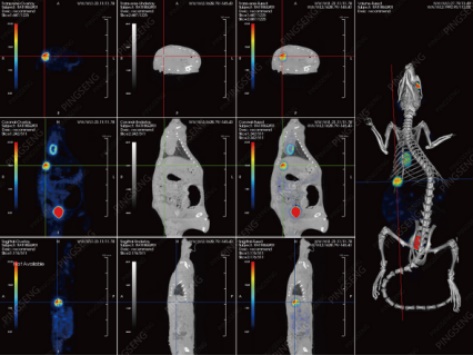

同年,研究者又使用Super Nova® PET/CT(平生醫(yī)療)觀察了此藥物和治療手段在乳腺腫瘤治療中的療效并發(fā)表了新論文[2]。研究者將乳腺腫瘤細(xì)胞種植到大鼠(母)的第二乳房脂肪墊中,并持續(xù)觀察直到腫瘤長到5-6mm,隨后注射微球進(jìn)行治療,同時(shí)與其他治療方式進(jìn)行對照。在此療效評估過程中,始終使用Super Nova® PET/CT來跟進(jìn)治療效果,結(jié)果顯示,131I-HCuSNPs-MS-PTX+Laser的方式對乳腺腫瘤的治療也十分有效。

大鼠乳腺腫瘤脂肪墊下種植,不同治療手段的PET/CT影響圖

(三維關(guān)聯(lián)顯示腫瘤位置;注射0.8mCi FDG1h后掃描10min)